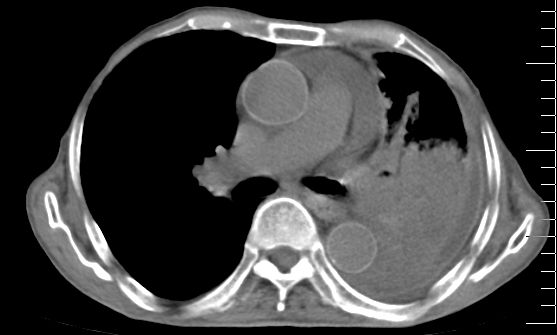

标题: CT10141:男、84岁,咳嗽、咯血1年。 [打印本页]

标题: CT10141:男、84岁,咳嗽、咯血1年。

支持左侧中央型肺癌伴下叶肺不张\\纵隔淋巴结转移.左侧包裹性胸腔积液\\心包积液.左侧少量胸腔积液..慢性支气管炎伴部分间质纤维化.

左肺中心性肺癌并肺不张,同侧 胸膜及心包转移,左肺癌性淋巴管炎

左侧中心型肺癌,左侧胸腔积液部分包裹,心包积液,肿膈淋巴结显示。

左肺中心性肺癌并左肺下叶肺不张,纵隔淋巴转移、同侧胸腔及心包积液(转移)。